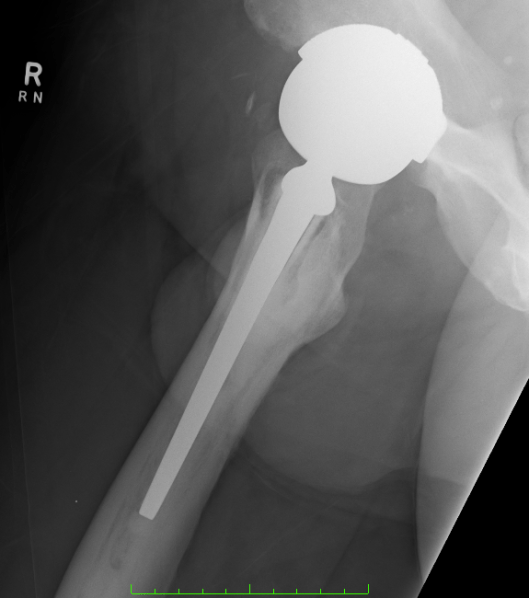

Had some new X-rays done today – two months since the last ones – seems to me that there is more osteolysis and bone loss – possibly some fragments but I am not a medical doc and I haven’t discussed these with the surgeon yet. Will do on the day of the surgery.

What is interesting is 3 radio-opaque spots showing up in the pelvic area – not sure what those are.

Quality of the photo’s below – OK for an iPhone 4 shot of the X-Rays held up by my son against a white background!

Will be taking iPhone and laptop to hospital to send you all the holiday snaps!

And these X-rays are much more modest that the last ones!